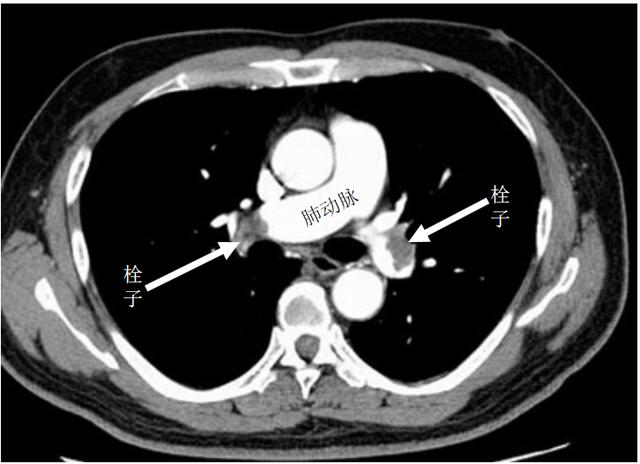

CT增强扫描明确肺栓塞,必须立即处理

如今,该病的病因、机理都已经很清楚:经济舱空间狭小,乘客的双腿活动受到了很大限制,下肢静脉回流不畅而形成血栓,时间一长,血栓范围和程度逐渐加大。飞机到达目的地后,乘客突然起立活动,静脉血栓脱落,随着血液回流到心脏继而到肺,引起肺动脉栓塞,这就患者突然发病、急剧死亡的原因。

所以说,所谓经济舱综合征,其实就是“下肢深静脉血栓形成”(DVT),并继而引起“肺栓塞”(PE),DVT与PE已被认为是同一疾病的不同阶段,目前常将其统称为静脉血栓栓塞症(VTE)。